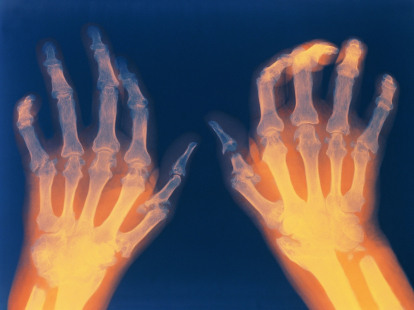

W zakresie dietetyki klinicznej poruszamy temat żywienia w kamicy nerkowej oraz zastosowania diet wegańskich w reumatoidalnym zapaleniu stawów (RZS).